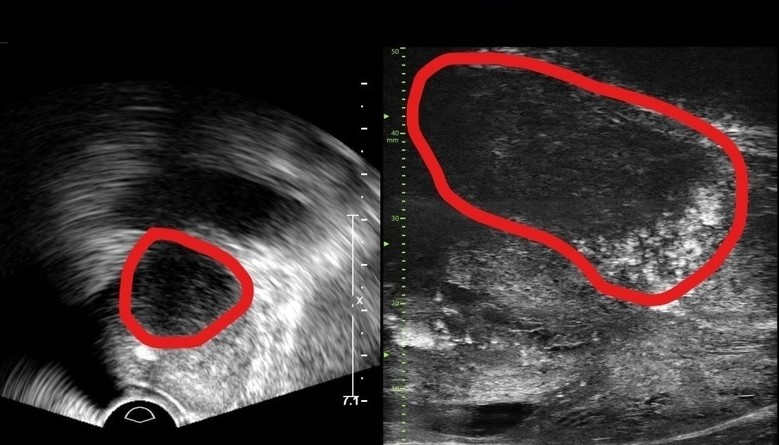

| ▲기존 전립선 초음파 사진(좌) 및 마이크로 초음파 사진(우). 기존 초음파는 전립선 부위(동그라미 친 부분)의 음영 차이로만 병변을 확인했지만, 마이크로 초음파는 높은 해상도를 통해 종양과 주변 조직의 모양까지 확인가능하다.(사진=분당서울대병원) |

기존의 경직장 초음파는 해상도가 낮아 전립선 종양, 특히 작은 암 병변을 감지하는 데 한계가 있었다. 하지만 마이크로 초음파의 높은 해상도와 실시간 영상의 시각화는 자기공명영상(MRI)으로 발견할 수 없는 전립선암을 찾을 때도 충분히 기여할 것으로 기대하고 있다. MRI 검사 보다 환자의 신체적, 심리적, 경제적 부담도 적을 수밖에 없다.

29MHz 마이크로 초음파를 사용하는 이 장비는 전립선과 주변의 해부학적 구조를 선명히 표시하고 표적 조직검사를 유도한다. 의심 영역을 실시간으로 확인하면서 전립선 조직의 미세한 변화와 병변을 식별하고 조직검사 채취를 위한 바늘을 정확한 위치에 삽입할 수 있다는 장점이 있다.